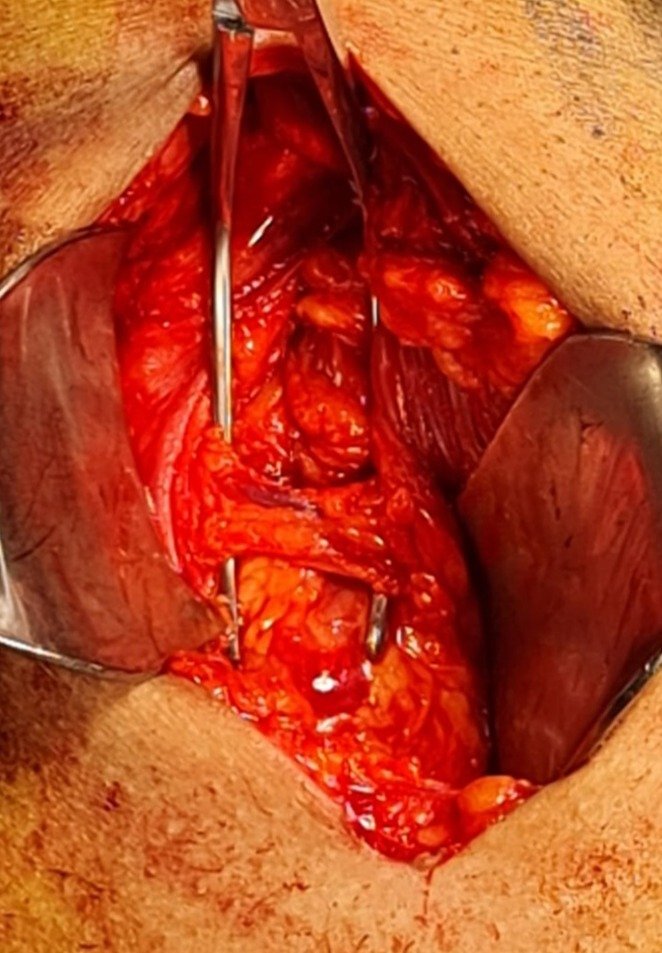

La arteria circunfleja: el riesgo incómodo en el abordaje por vía anterior de cadera

-Una de las razones por la que muchos cirujanos evitan esta técnica, es por la necesidad de manejar la arteria femoral circunfleja anterior. Es una rama de la arteria femoral profunda, y hasta en 20% de los casos, directamente de la femoral. Por lo tanto tiene gran presión y flujo.

-Tiene 3 ramas, ascendente, transversa y descendente. Y dependiendo de la anatomía de cada paciente podemos toparnos 1 paquete vascular o 2. Incluso 1 o 2 “Y” vasculares.

-Requiere experiencia del cirujano en manejo de paquetes vasculares. Puede ligarse, cliparse o fulgurarse. Una arteria que ya se bloqueó su flujo y se corta para continuar con la cirugía, pero de repente comienza a sangrar, puede ser difícil de encontrar ya que cada cabo se retrae.

Nuestra técnica para evitar el sangrado

-En lo personal, después de manejar todas las opciones, en el Centro de Reconstrucción de Extremidades de Médica Campestre en México | León, Guanajuato, hemos tenido los mejores resultados con la fulguración directa y suficiente del paquete completo sin esqueletizar los vasos.

-Recomiendo encontrar las estructuras, colocar una pinza vascular debajo de ellas para tensarlos y a la vez separarlos del fondo. En este momento se puede usar el electrocauterio bipolar.

-En caso de usar el monopolar se puede realizar un fulguración en espiral. Importante que el equipo de electrocauterio se encuentre en “fulgurar” y no en “disecar”.

-Si se usa monopolar directo o con ayuda de una pinza disección, es esperado encontrar contracciones reflejas de la musculatura cercana, en especial del recto femoral.